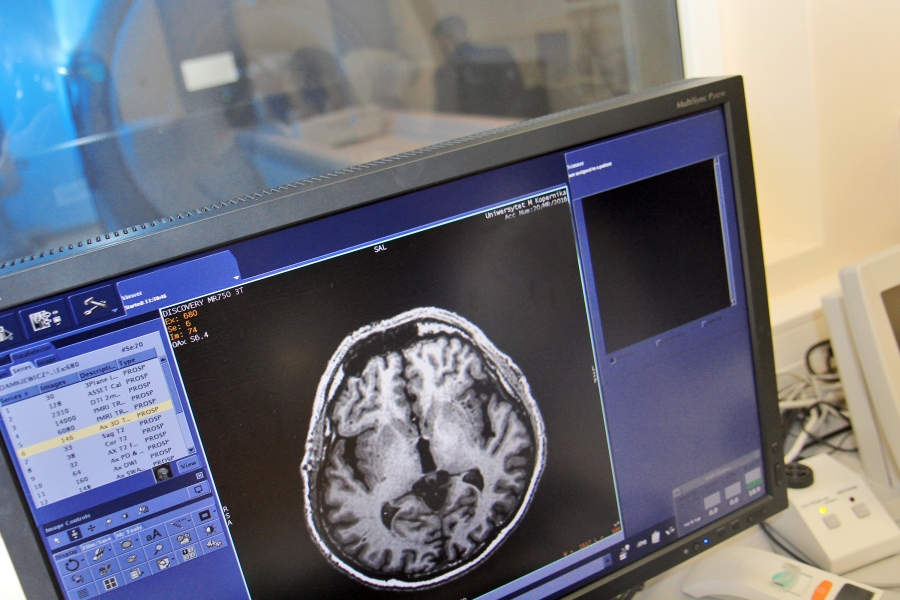

The discovery lay a foundation stone upon which a number of research studies employing modern neuroimaging techniques, for example magnetic resonance (fMRI), was based. Despite the dynamic development in this area, numerous key problems still remain unresolved. Punishment-avoidance learning is one of them.

In order to answer the formulated questions, the scientist performed a study using an fMRI scanner. 22 healthy volunteers who participated in the study were expected to complete a task using the trial and error method in the gain and loss context. Successful task completion required constant monitoring of results of their decisions. Every other second, their brain images were collected providing information concerning the areas more or less engaged in the process.